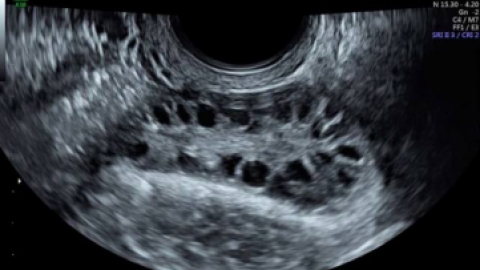

多囊卵巢综合征:超声辅助诊断新技术

目前,多囊卵巢形态多由超声医师主观判断,无法对卵泡总数、卵泡大小或卵巢体积进行精细量化。作者指出,超声检查可用于月经周期异常女性卵巢的常规评估,主要目的为诊断多囊卵巢综合征(PCOS)。的小卵泡,和/或卵巢体积增大(>10ml)。的测量数值与二维数据相比,结果更可靠准确,可应用于辅助生殖过程中的卵泡追踪或卵巢储备的评估...

窦卵泡计数 想要升级当妈,测测生育能力强不强

所以卵子绝对是不可再生资源,大龄女性在备孕前就要看看卵子的储备量是不是还充足,如果充足,那就说明你的生育能力还是很强的。测卵巢储备,看生育能力一般医院最常用的就是经阴道超声进行窦卵泡计数(AFC)。窦卵泡是指那些在阴道超声下可以看到的直径在2~这些人需要测测生育能力如果女性确实出现卵巢储备功能下降,那么很遗憾目前没有任...

测试卵巢储备的重要性卵巢储备测试一目了然卵巢储备的主要测试是卵泡刺激素(FSH),雌二醇,抗苗勒氏激素(AMH)和卵巢窦卵泡计数。卵巢储备的主要测试是卵泡刺激素(FSH),雌二醇,抗苗勒氏激素和卵巢窦卵泡计数。结合FSH测试,可以通过测试雌二醇(雌激素的一种重要形式)来评估女性的卵巢功能和卵的质量。超声上可见的窦卵泡数...

AMH和窦卵泡计数是个啥东西?窦卵泡计数的正常值是多少?多囊卵巢的窦卵泡计数应该是什么值?在PCOS窦卵泡是多的,一个里面的起码大于12个,这个量比正常值大2~3倍左右。关于窦卵泡计数,大家确实也都在研究当中,每个生殖中心的观点可能都不太一样,咱们可以记一些异常值,比较主流的观点:一个是博罗尼亚卵巢反应不良专家共识,这...